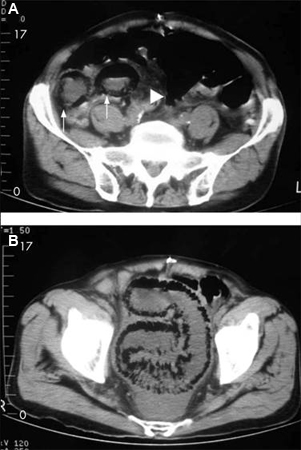

A TC fornece evidências da extensão do comprometimento intestinal decorrente da isquemia; ela é útil para diagnosticar isquemia mesentérica aguda, mas os achados podem ser inespecíficos na isquemia inicial.[39][40] Os primeiros sinais incluem espessamento da parede intestinal e dilatação luminal. Os sinais tardios incluem pneumatose (gás na parede intestinal) e gás mesentérico ou venoso portal, o que geralmente indica necrose intestinal.[32][41] Os outros sinais tardios incluem um intestino edematoso e um aumento variável do intestino cercado por líquido livre.[31] Pode mostrar espessamento da parede intestinal com sinais de impressão digital sugestivos de edema ou hemorragia submucosos, o que sugere um pior prognóstico.

[Figure caption and citation for the preceding image starts]: Homem de 84 anos que apresenta sintomas sugestivos de doença intestinal isquêmica: (A) Tomografia computadorizada (TC) abdominal que revela uma formação de ar circunferencial maciça e em forma de faixas como pneumatose intestinal (setas) e edema pronunciado da gordura mesentérica (ponta de seta) ao redor das alças intestinais necrosadas; (B) Outra secção da TC abdominal mostrando pneumatose segmentar longa do intestino delgadoLin I, Chang W, Shih S, et al. Bedside echogram in ischaemic bowel. BMJ Case Reports 2009:bcr.2007.053462 [Citation ends].